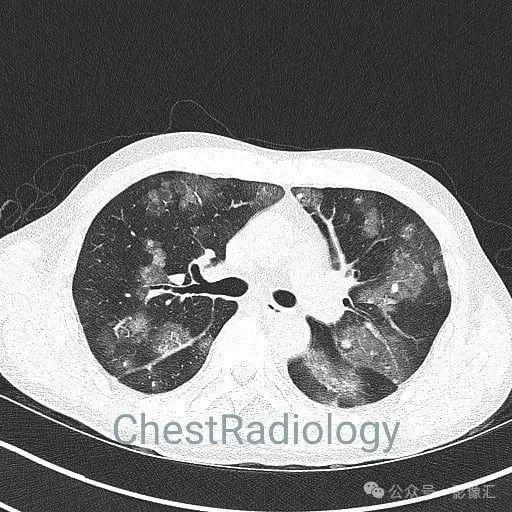

咯血患者,肺部弥漫磨玻璃,细节决定成败?

成年男性,咯血,细节决定成败,你看到了吗?欢迎评论区留言